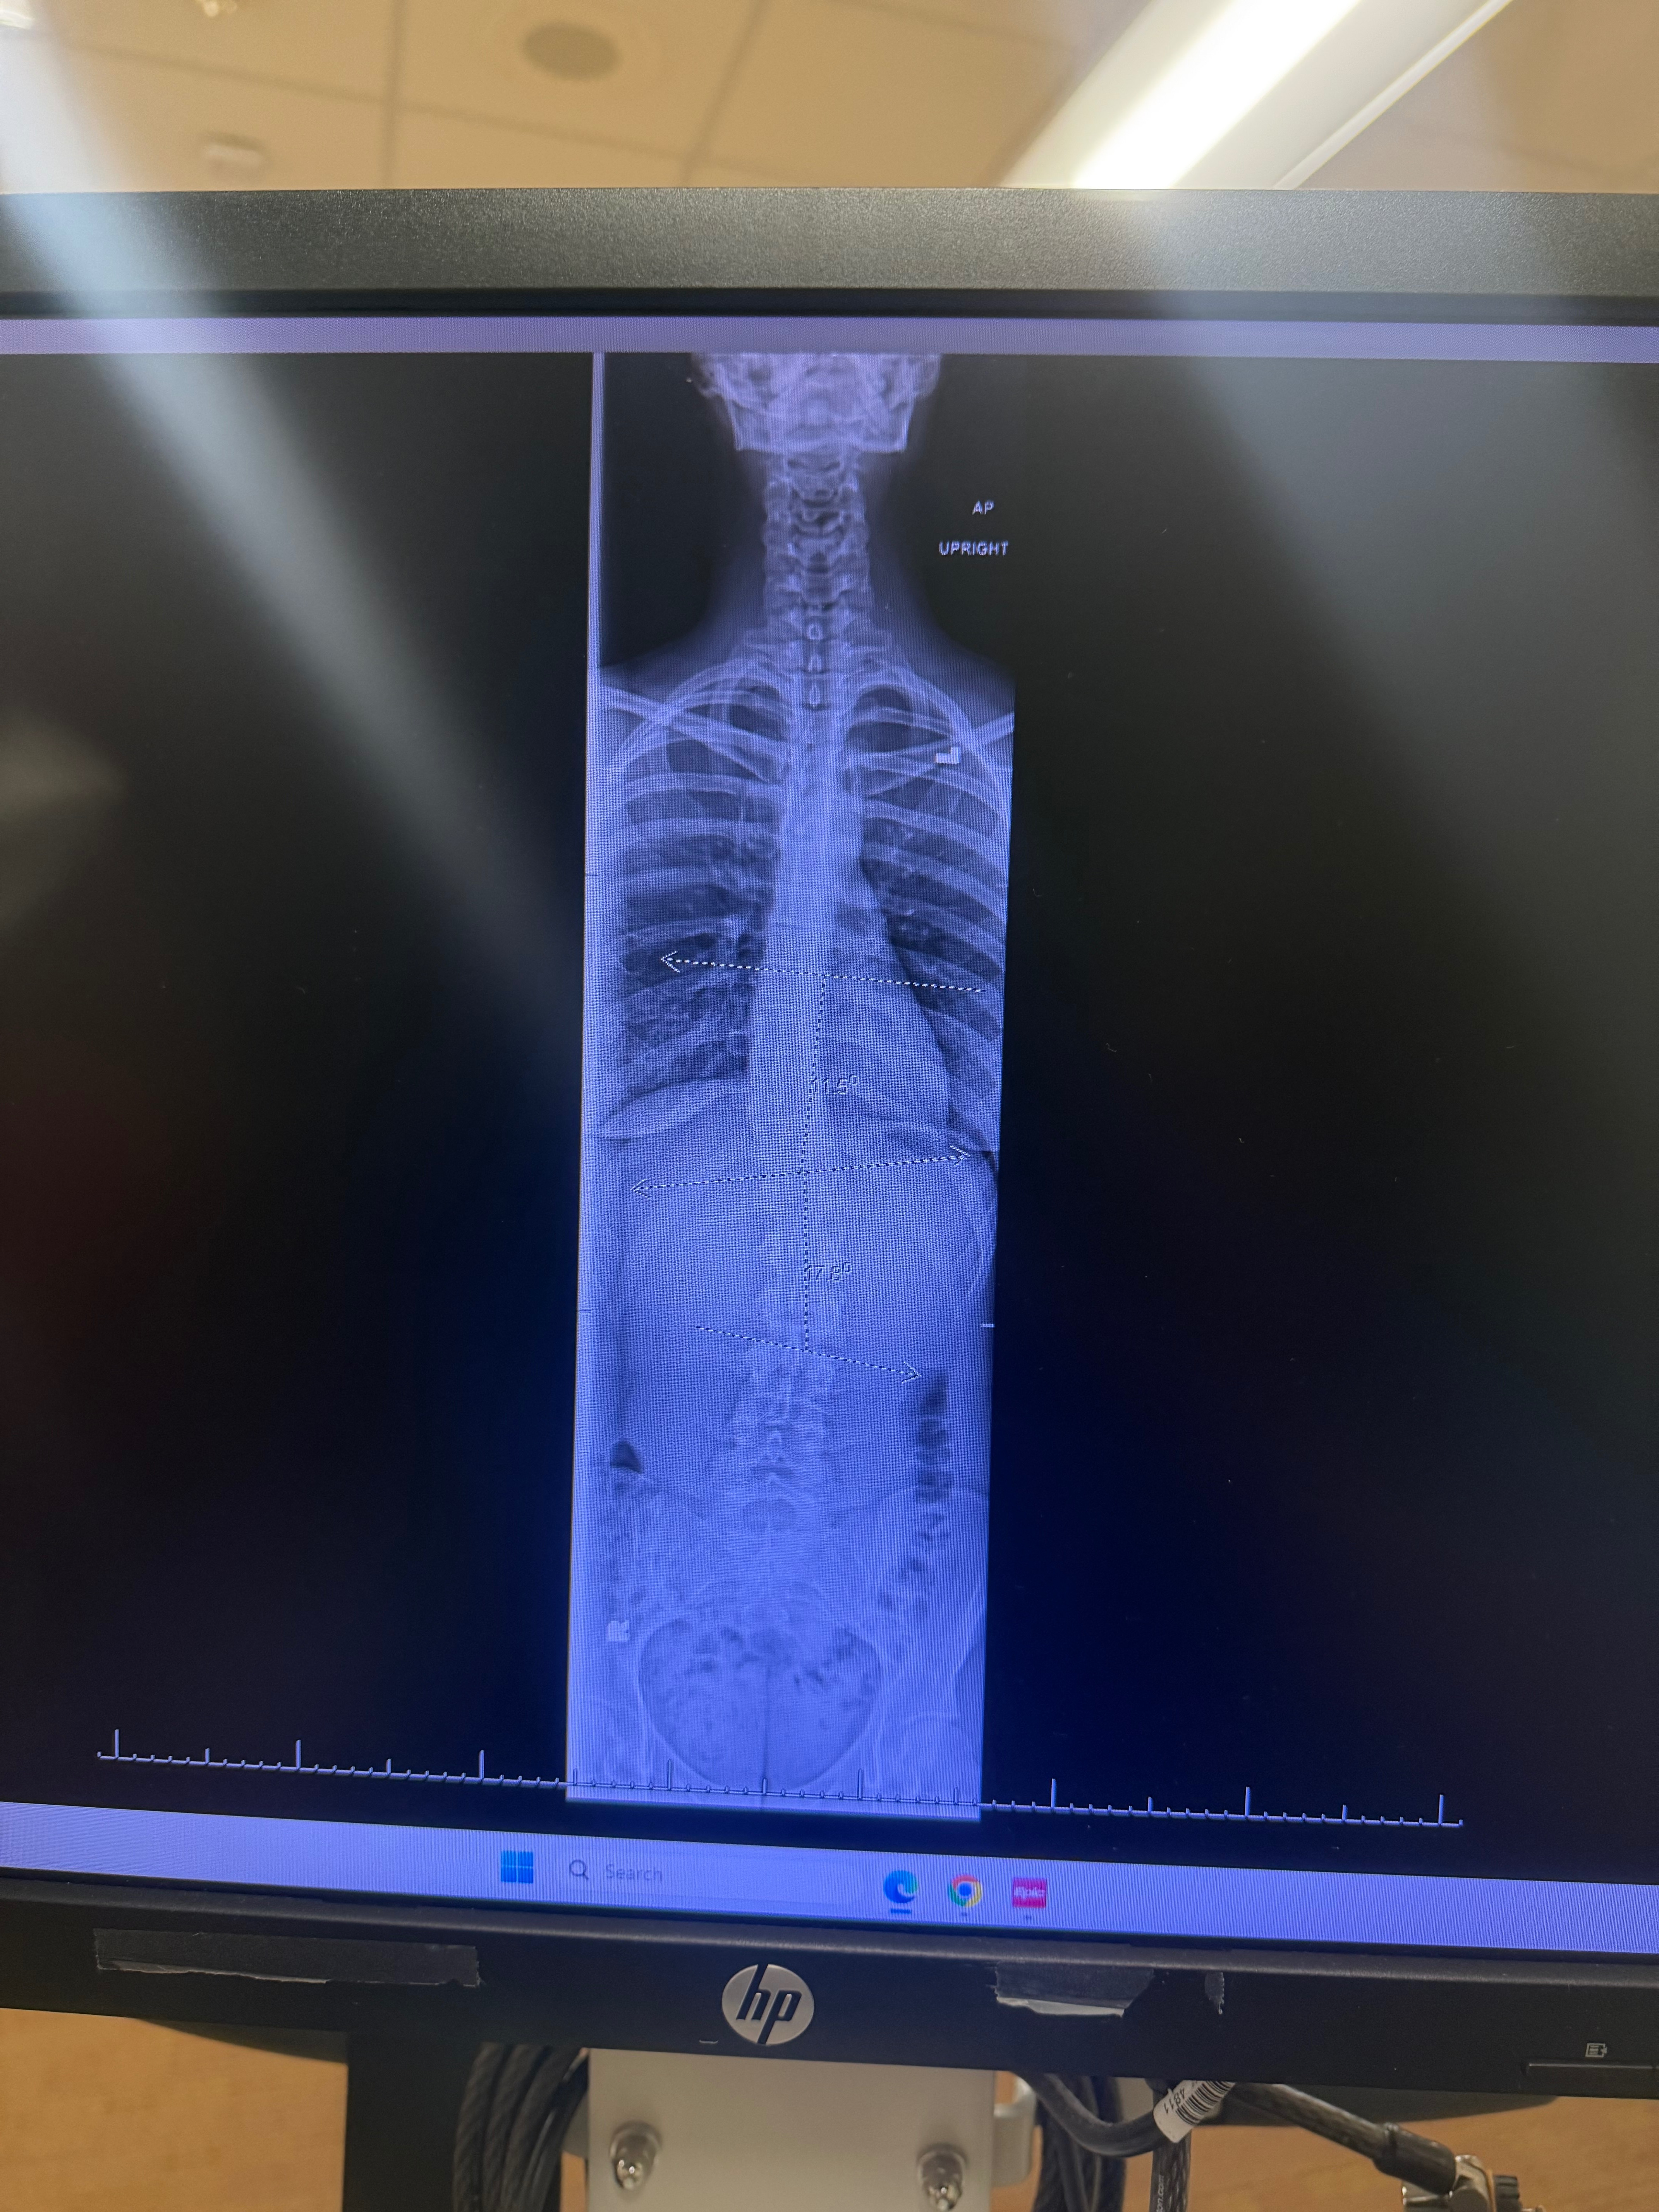

To add I am experience serious recovery from falling out of a red truck in Thailand and crashing on my left side of my body.